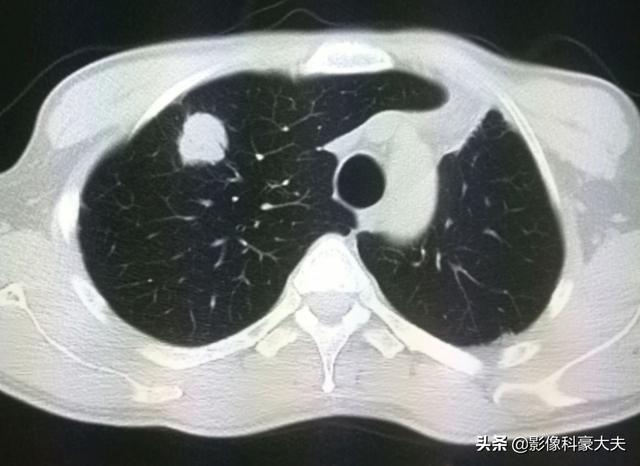

肺炎は抗生物質で治り、その後、左肺がんの摘出手術。手術から2年半後、右肺に転移が見つかった:

このタイプの乏血転移を治療する方法がある!プローブを腫瘍に挿入し、瞬間的に高周波高温アブレーション療法でがん細胞を焼灼する: